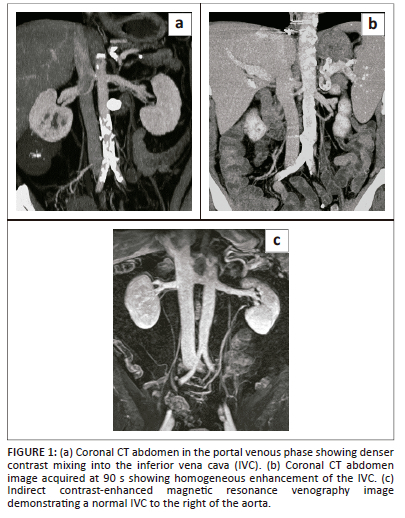

Post-contrast CT of the abdomen is the preferred and most commonly used modality for the evaluation of the IVC. The inferior vena cava is often evaluated on routine CT abdomen and pelvis, which is usually obtained in the post-contrast portal venous phase at 60 s - 70 s. However, in the portal venous phase, there is differential contrast enhancement of the renal and suprarenal IVC compared with the infrarenal portion. Venous return from the kidneys result in denser contrast in the renal and suprarenal IVC. Thus, portal venous phase imaging may result in incomplete opacification of the infrarenal IVC and may show admixture artifact. Increasing the delay time for CT image acquisition to 70 s - 90 s after intravenous contrast administration allows homogeneous opacification of the infrarenal IVC (Figure 1). With the advancement of multidetector computed tomography (MDCT) scanners, multiplanar reformation can be obtained, which is often useful in delineating IVC disease.1,2,3,4

The use of MRI not only avoids the risk of ionising radiation but also helps in a more reliable detection of the presence and delineation of tumour thrombus extent when compared with CT. However, anaesthesia for the paediatric population, cost and limited availability are challenges for the routine use of MRI for IVC assessment. Evaluation of the IVC can be performed using post-contrast three-dimensional breath-hold T1-weighted MR images. Balanced steady-state free precession is another useful MRI sequence.2,3 Magnetic resonance venography (MRV) is often used for evaluation of venous structures mostly in the brain but can also be used for evaluation of the IVC. It can be obtained without gadolinium, using time of flight (TOF) or phase techniques.5,6 The TOF sequence uses the flow related enhancement technique where stationary tissues are saturated and only protons flowing into the slice can generate signal. Application of a pre-saturation band to the artery proximal to the slice can avoid signal from inflowing arterial blood. The TOF sequence can be a 2D or 3D acquisition, but 3D TOF is rarely used for body MRV because of the long scan time. 2D TOF is prone to respiratory artifact and has poor resolution. In addition, if the vein imaged is oriented along the plane of imaging, there can be loss of signal because of saturation of inflowing protons.5 The phase contrast technique uses phase shift and velocity differences of moving protons for imaging. Sensitivity to a particular vessel is based on velocity encoding. Vessels with flow velocity close to velocity encoding are more sensitive. Contrast-enhanced MRV can be performed, and is superior in the evaluation of the IVC, as it depends on gadolinium rather than flow phenomena and hence is less prone to artifacts.7 It can be performed with an indirect or direct approach. For the indirect approach, contrast is injected in a peripheral vein with imaging performed during the early equilibrium phase (Figure 1). A large amount of contrast is required because of the dilution of contrast. This method is not preferred in abdominal MRV because of misregistration from respiratory motion. Using the direct approach, diluted contrast is continuously injected upstream of the venous territory. The amount of contrast required is considerably less because of targeted injection of dilute contrast, but results in good image resolution as a result of a superior signal-to-noise ratio.5,8 The 3D contrast-enhanced MRV techniques have a wide range of applications including evaluation of IVC abnormalities.7